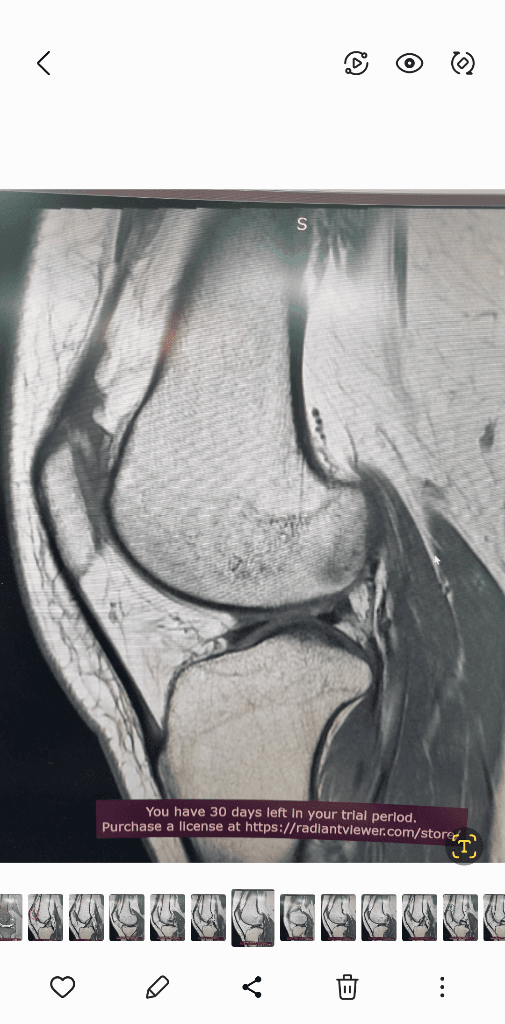

1. 추벽이 아닙니다.

2. 슬개골 관절면에 외상으로 인한 골수부종입니다.

3. 관절면 손상여부는 첨부해주신 영상만으로 알 수 없습니다